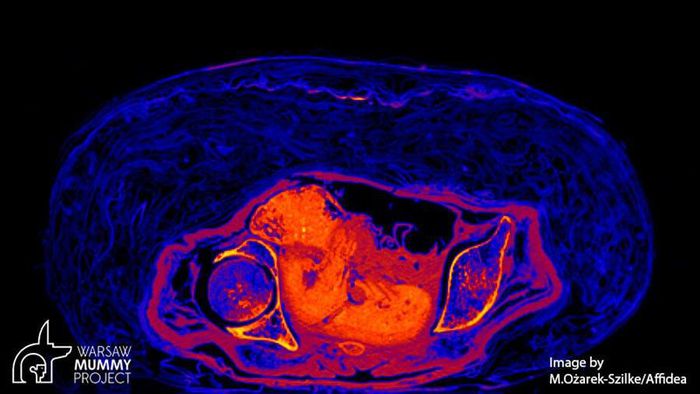

Được lưu giữ trong Bảo tàng Quốc gia ở Warsaw, Ba Lan từ năm 1917, một xác ướp Ai Cập cứ ngỡ thuộc về linh mục nhưng thực tế là của một thai phụ.

Vào năm 1826, một xác ướp Ai Cập và quan tài được tặng cho Đại học Warsaw, Ba Lan. Sau đó, chúng được lưu giữ và bảo quản trong Bảo tàng Quốc gia ở thành phố Warsaw kể từ năm 1917.

Theo các chuyên gia, xác ướp có niên đại hơn 2.000 năm tuổi. Trong suốt nhiều năm, họ cứ ngỡ đó là thi hài của một linh mục Ai Cập cổ đại tên là Hor-Djehuty.

Tuy nhiên, bí mật "động trời" về giới tính của xác ướp trên được hé lộ khi các chuyên gia sử dụng kỹ thuật chụp cắt lớp vi tính vào năm 2016.

Kết quả cho thấy xác ướp không phải là của linh mục Hor-Djehuty. Thay vào đó, thi hài thuộc về một phụ nữ tử vong khi mang thai. Thai nhi đang ở tuần thai thứ 26 - 30.

Sau khi tử vong, thai phụ trên được ướp xác cùng với bào thai trong bụng. Từ đây, các chuyên gia đặt ra hàng loạt câu hỏi như: người phụ nữ này là ai? Tại sao bà được ướp xác cùng với thai nhi?...

Trước sự việc này, nhà khảo cổ học Wojciech Ejsmond thuộc Học viện Khoa học Ba Lan cho biết bào thai đã không được lấy ra khỏi bụng mẹ như trong quá trình ướp xác thông thường.

Chính vì vậy, tính đến thời điểm hiện nay, đây là xác ướp duy nhất được ướp xác với thai nhi nguyên vẹn trong bụng mẹ.

Thai phụ này được ướp xác rất cẩn thận với một bộ bùa hộ mệnh. Điều này cho thấy bà xuất thân từ tầng lớp giàu có hoặc có địa vị cao trong xã hội.

Các nhà nghiên cứu tin rằng việc phân tích các mô mềm được bảo quản của xác ướp có thể mang lại một số manh mối giúp tìm ra nguyên nhân tử vong của thai phụ.

Dù vậy, một số chuyên gia đưa ra giả thuyết người phụ nữ có thể đã gặp một số vấn đề về sức khỏe trong quá trình mang thai. Điều này khiến bà tử vong trong thời gian thai kỳ.